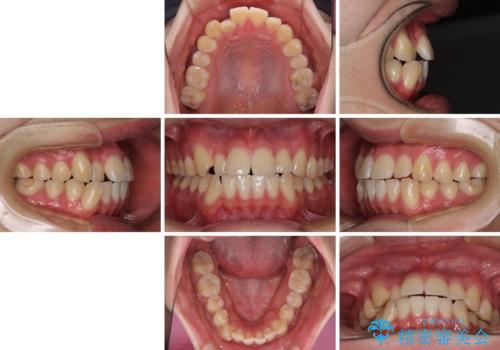

八重歯と前歯のクロスバイト ワイヤー装置で短期間矯正

- 八重歯を気にして来院された患者様です。

上顎側切歯(前から2番目の歯)が内側に転位している歯列は、インビザラインでは排列が困難であることが多いため、期間を短く、より良い仕上がりとするため、ワイヤー装置にて矯正治療を行うこととしました。

治療開始の頃は、食事や歯磨きが慣れず、装置が頻繁に脱落しましたが、2,3ヶ月ほどで慣れ、その後は1年ほどで治療を終えることができました。